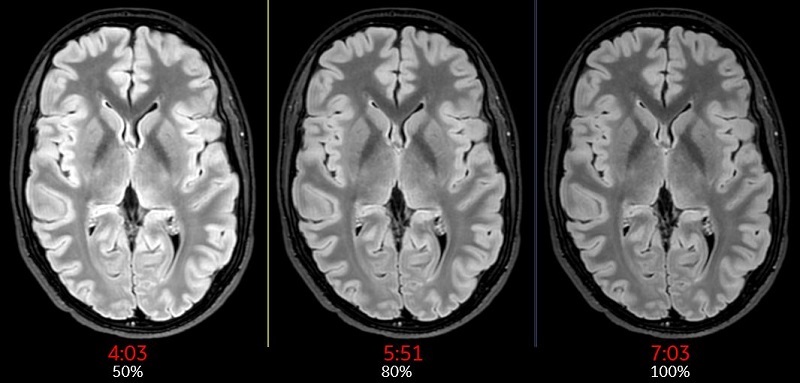

Slice Resolution %

The Slice Resolution % value is used to define the zero-padding on both sides of the kz direction in k-space. For example, when Slice Resolution (%) is set to 50, it is equivalent to the old ZIP x 2 Imaging Option. When Slice Resolution (%) is set to 25, it is equivalent to old ZIP x4 Imaging Option.

Use Slice Resolution % to reduce the number of slice encoding for 3D acquisitions to decrease the scan time. The tradeoff is reduced image resolution.

Slice Resolution% is annotated next to the Slice thickness annotation in the lower left corner of the image.